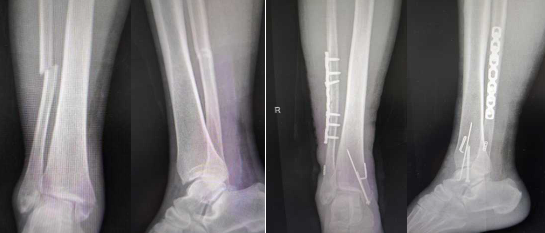

近日,英山县医共体总医院(县人民医院)骨一科成功开展“弹性固定”新技术,为踝关节骨折患者提供了更优治疗方案。该技术尤其适用于伴有下胫腓联合损伤的复杂踝关节骨折,通过弹性袢钢板固定系统实现符合人体生物力学的“弹性悬吊”,在确保稳定的同时,允许早期生理微动,从而助力患者更快恢复功能,并有效避免二次手术。

建筑工人杜先生在工作中不慎从高处坠落,导致踝关节严重骨折伴下胫腓联合损伤。若采用传统螺钉固定,他将面临术后长时间无法负重且骨折愈合后仍需再次手术取出螺钉的漫长过程。经该院骨一科团队评估,为其施行了弹性袢钢板固定术。术后,杜先生在医生指导下得以早期开始踝关节活动,康复进程显著加快。更令他欣慰的是,骨折愈合后无需二次手术取钉,为他节省了时间与经济成本,得以提前数月重返工作岗位。

这些成功案例的背后,得益于该院骨一科成熟开展的弹性袢钢板固定技术(如Endobutton/TightRope系统)。以往,治疗此类损伤常采用“下胫腓螺钉”固定,虽能提供稳定,但患者术后需长时间避免负重,严重影响日常生活,且绝大多数患者需在骨折愈合后再次手术取出螺钉,不仅带来二次创伤,也增加了经济负担。与之相比,弹性袢钢板系统由高强度缝线与微型纽扣钢板组成,生物相容性良好,可长期留存体内,通常无需二次手术取出。其核心优势在于“弹性悬吊”设计,能在维持稳定的同时允许关节必要的生理微动,使得患者可以更早开始康复锻炼,有效减轻关节僵硬与肌肉萎缩,并降低了因螺钉松动、断裂等引|发并发症的风险。